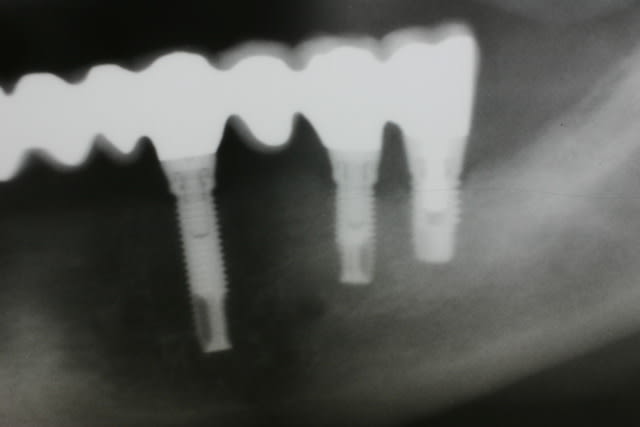

Radiologiquement ça pourrait paraître ok sauf que

1. douleur au niveau des implants distaux stt le 46 gros diamètre court

2. ça jute déjà un peu autour des implants

3. et pourtant un antagoniste amovible réputé peu puissant

Tu vois pourquoi je veux de all on 4 ou 6

Img 3369 aq5eir - Eugenol

Img 3370 dgaejj - Eugenol

Img 3371 vc5xos - Eugenol

Img 3368 sr2xhd - Eugenol